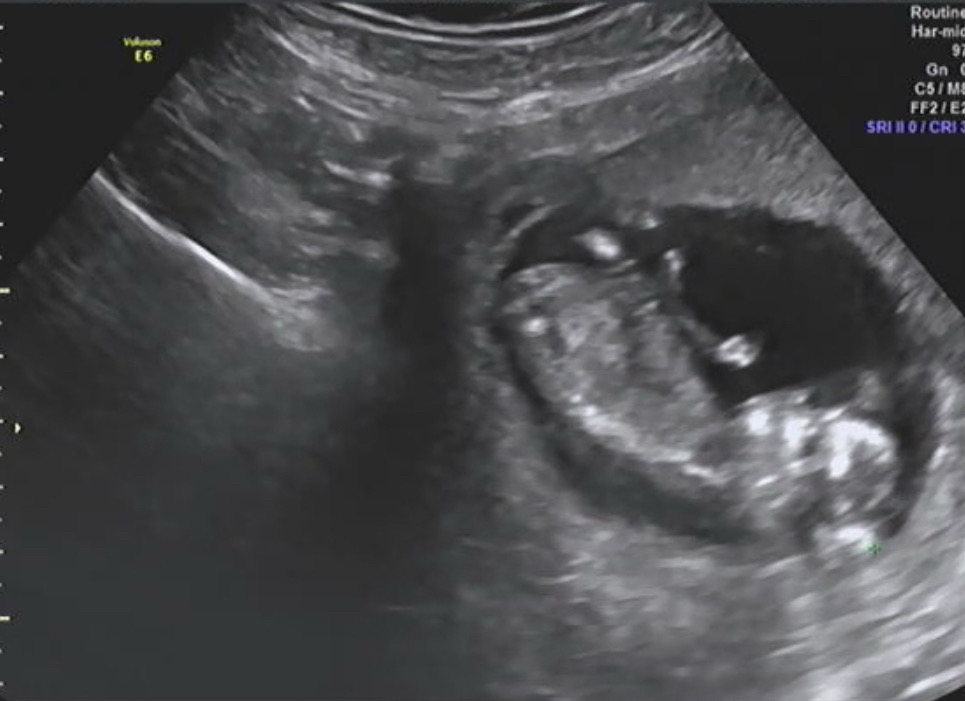

12주5일차 각도법 좀 봐주세요ㅠㅠ

아들일까요? 딸일까요?

아들같아요

딸이래요...